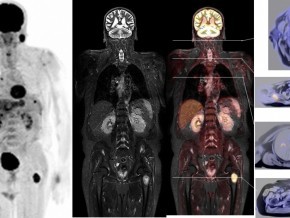

• Khám sức khỏe/ tầm soát:DWIBS

Được trang bị các thiết bị hiện đại của hãng Siemens, bao gồm MR-PET và máy chụp nhũ ảnh 3D (3D Mammography).